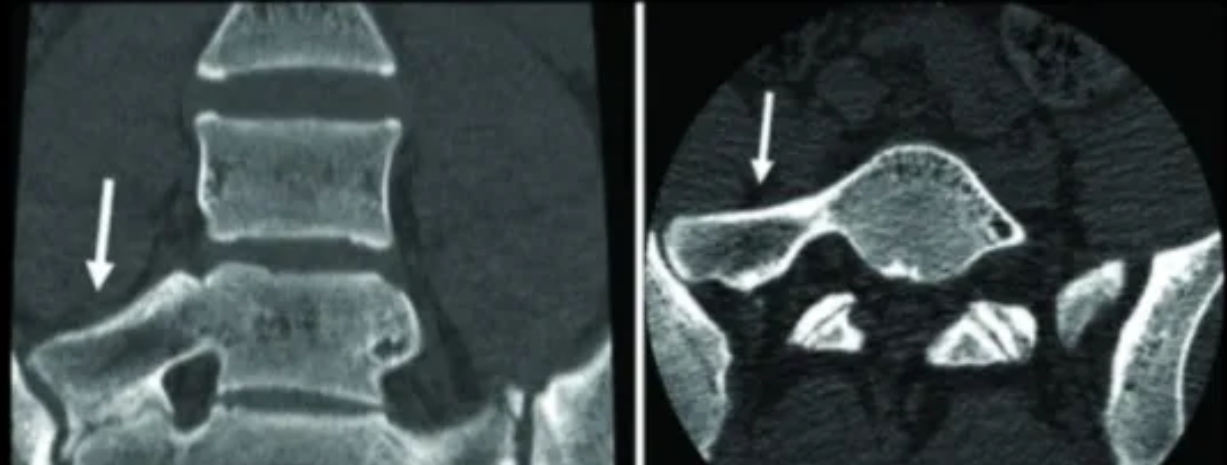

IIIa型:三维CT显示右侧横突与骶骨嵴融合

IIIb型:双侧横突与骶骨嵴融合